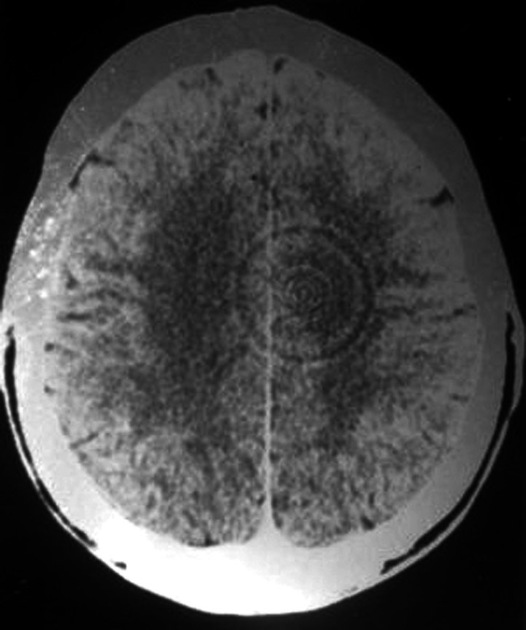

脑部扫描的环形伪影脑部扫描的环形伪影